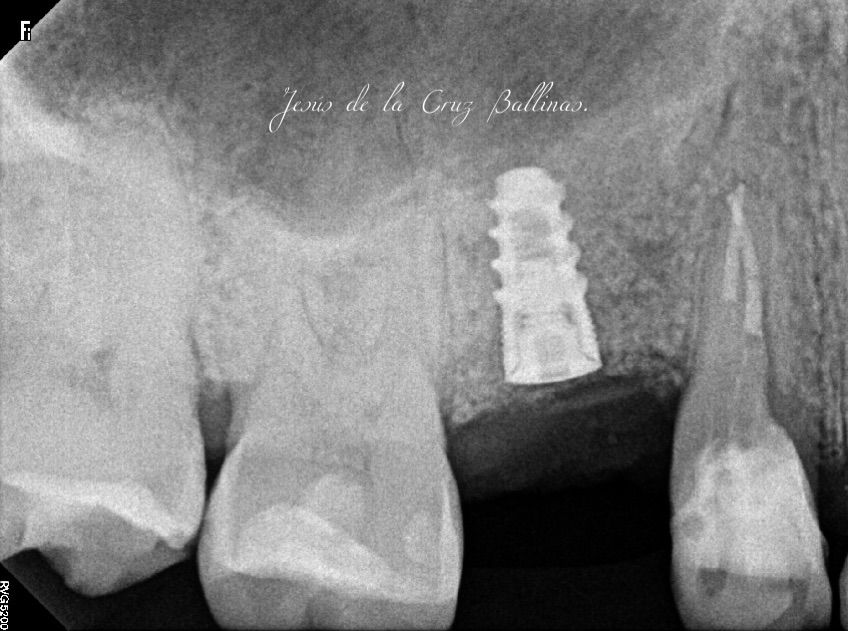

Especialista en Implantología Oral quirúrgica y protesica, cédula de especialidad: 12411844

La especialidad en Implantología Oral se enfoca en sustituir órganos dentarios perdidos por implantes dentales mediante una fase quirúrgica y una fase protesica y de esta manera devolver la función, estetica y confort dental del paciente.